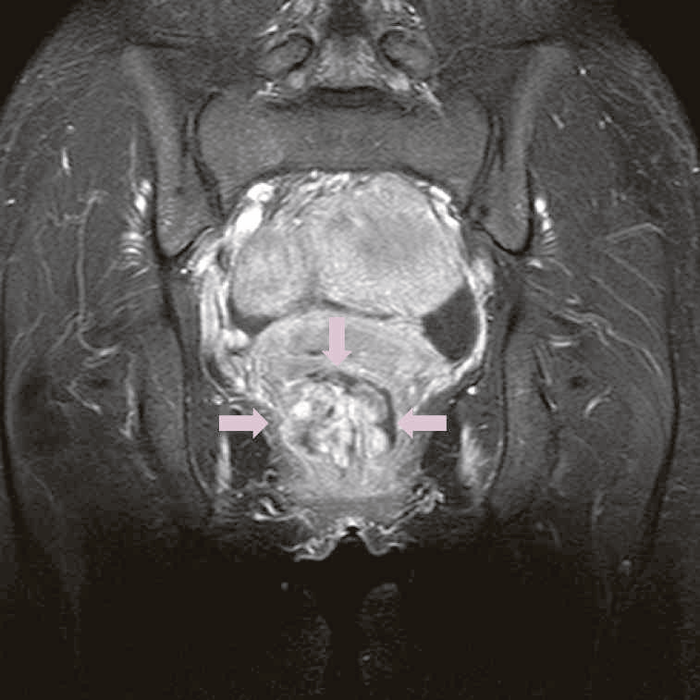

精査で施行したCT,MRIで痔瘻癌が疑われた。

図41 腹部骨盤MRI

診断時のMRIでは直腸下部壁内から周囲にhigh intensity areaが拡がり,右側には痔瘻の瘻管を認めた。high intensity areaは前方で前立腺や陰茎海綿体付近まで広がっていた。

図38 骨盤部MRI

術前の骨盤部MRIでは右側の痔瘻瘻管と,左側の瘻管,周囲のリンパ節腫大を認めた。

明らかな癌を示す所見は不明であった。